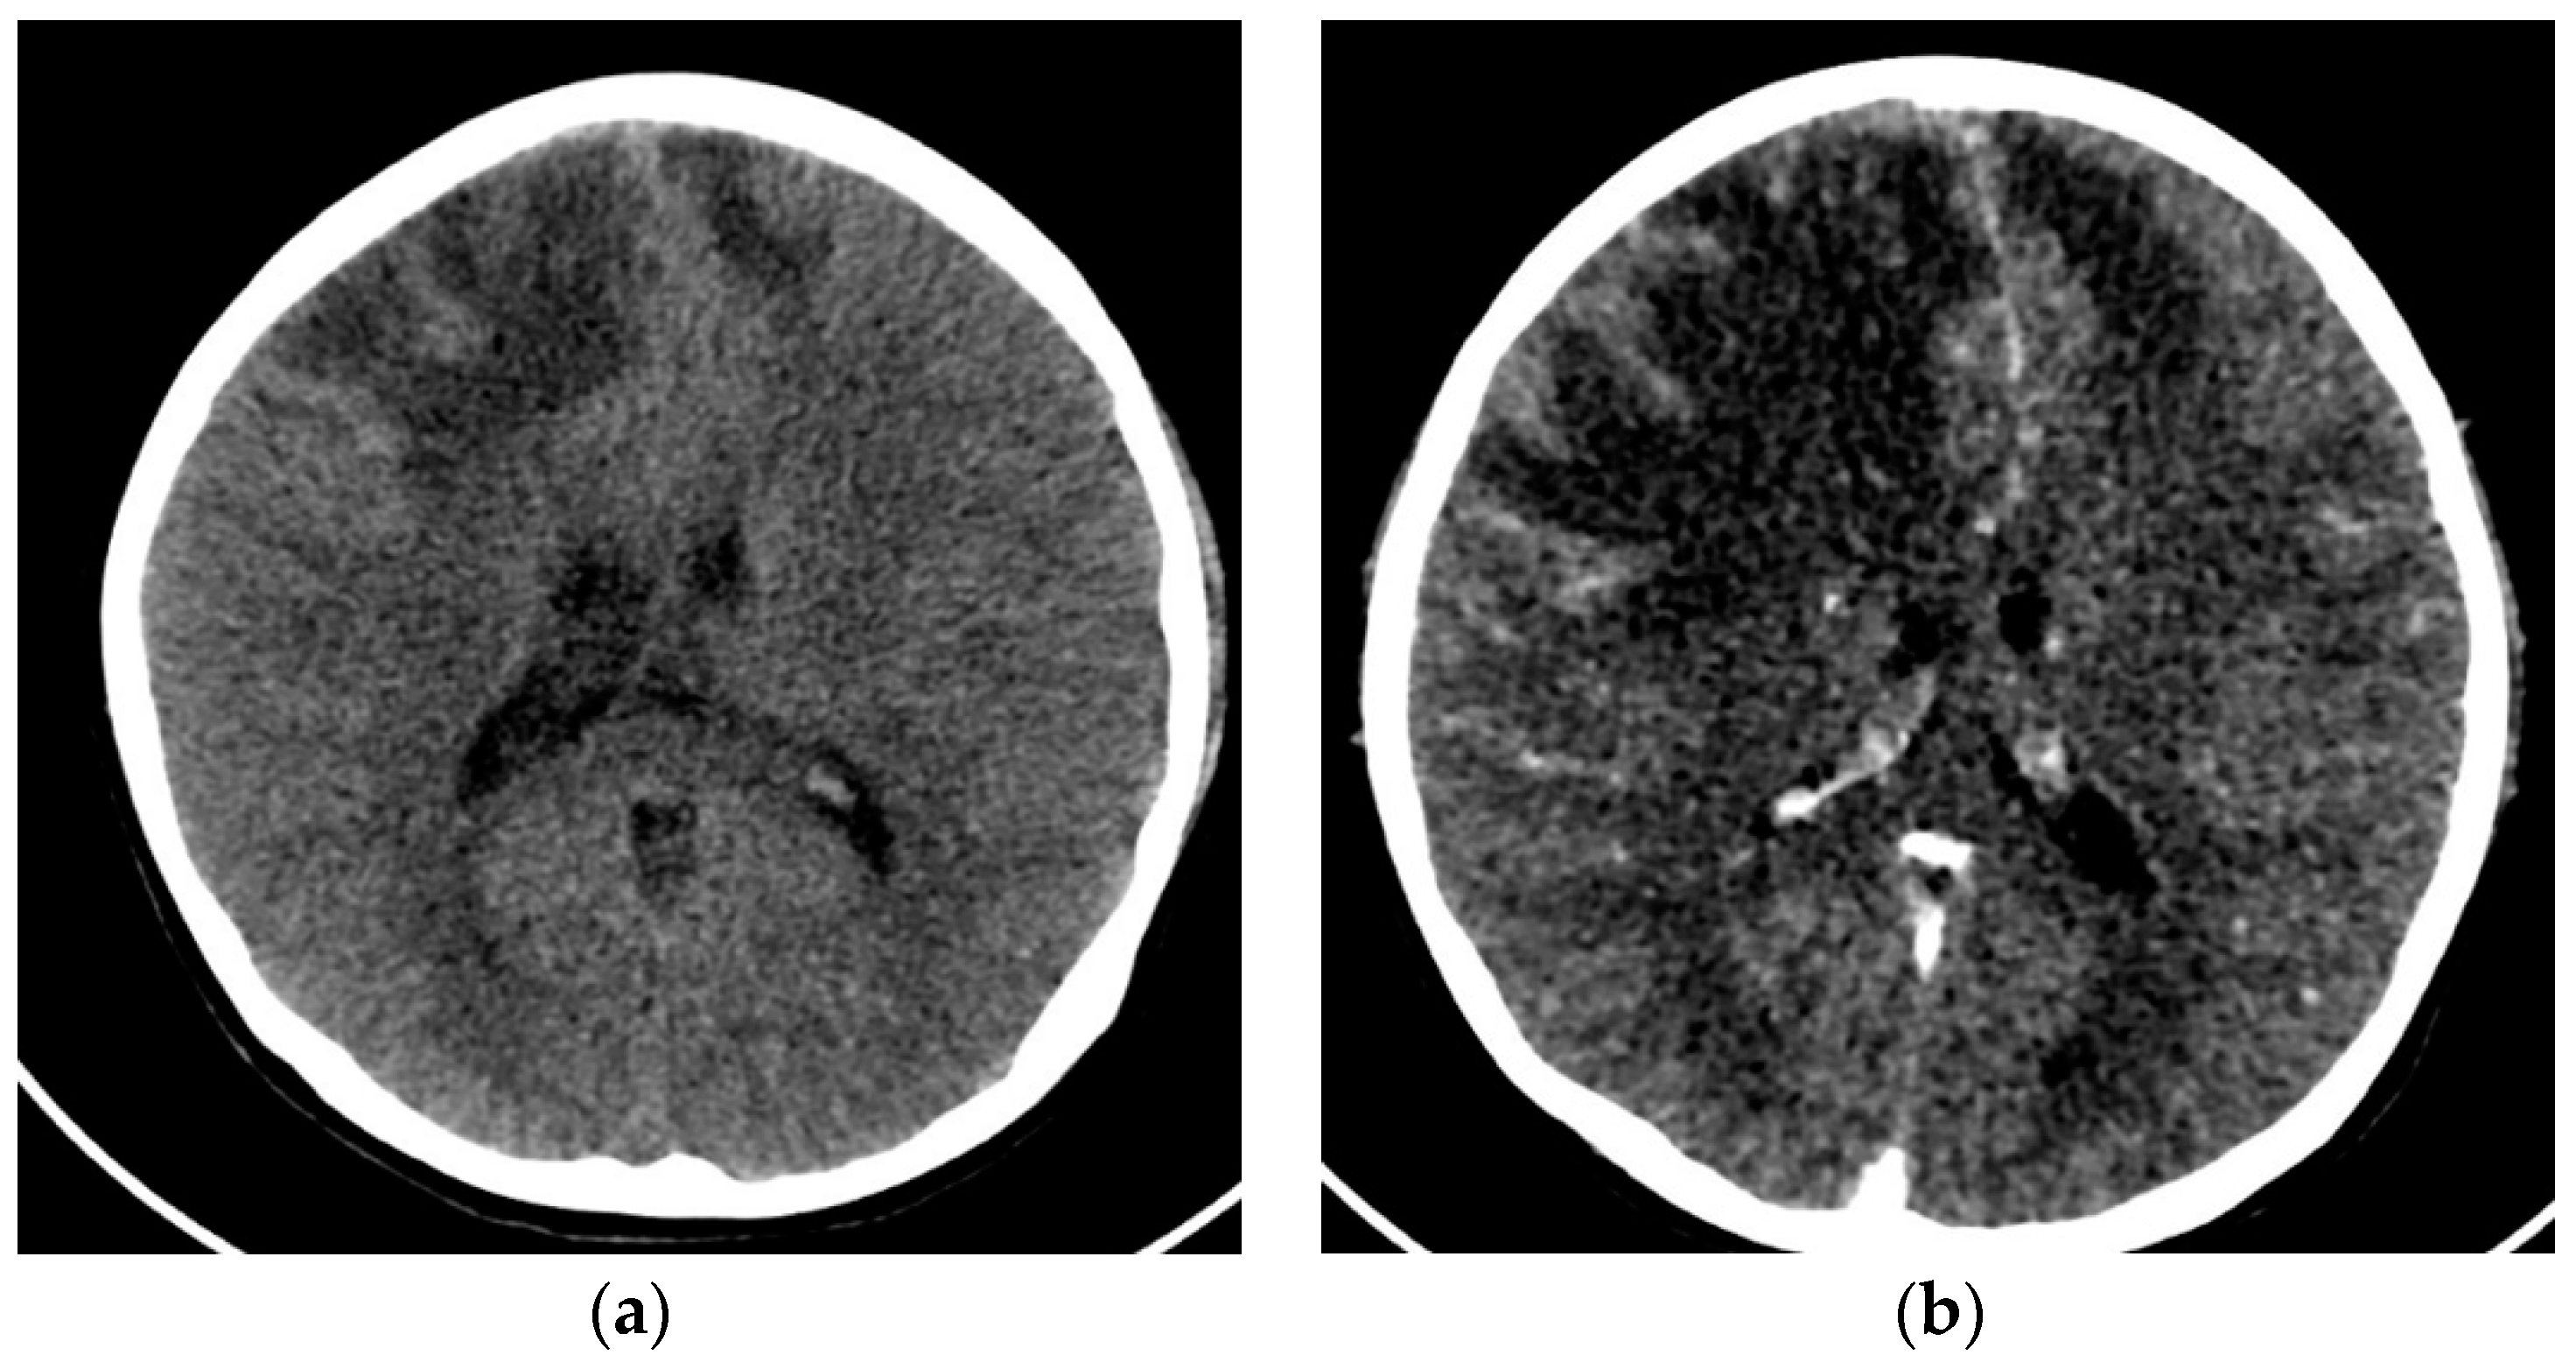

2.3. Case 3